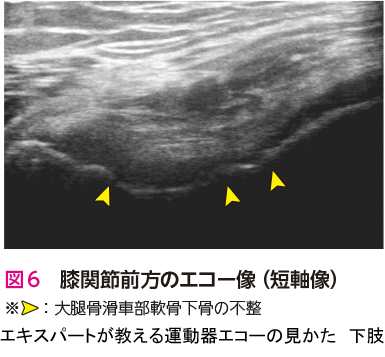

人工関節置換術を施行した症例です.エコー検査での膝関節前方(長軸像)では,膝蓋骨の骨棘と関節水腫を観察できます.また,膝関節内側(長軸像)では,内側側副靭帯浅層の直下に骨棘と内側半月板を観察できます.骨棘は大腿骨と脛骨から大きく張り出しています(図1🅑*).